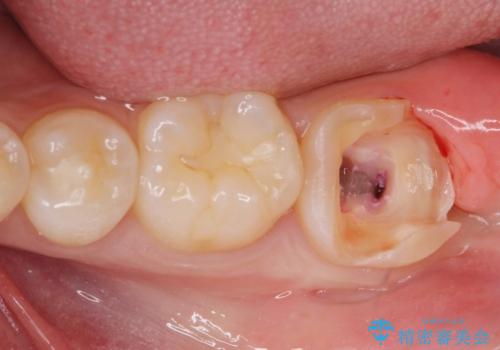

- 歯が痛くなり、他院で治療してもらったところ不信感があり、当院に受診に来られました。

神経をとる処置をされた形跡がありましたがまだ虫歯が残っていたので全て取り除き、壁を立てて根管治療ができる状態にして、根管治療・ジルコニアクラウンで治療を行いました。

虫歯除去、根管治療は拡大鏡やマイクロスコープを用いて治療を行っています。